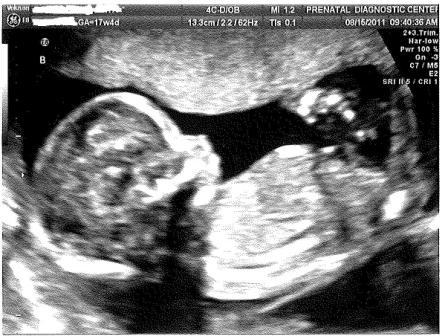

It’s a Girl and Another Girl! This entry was posted on August 25, 2011, in Pregnancy and tagged baby, clomid, kick, kicking baby, Pregnancy, sonogram, twin, twin girls, twin pregnancy, twins. Bookmark the permalink. Leave a comment We are proud to announce we are having 2 girls! Here’s Baby B kicking Baby A. No kidding, we actually watched her kick her sister in the head during the sonogram! Here’s a sweet sonogram of Baby B. home Share this: Share on Facebook (Opens in new window) Facebook Share on X (Opens in new window) X Share on Pinterest (Opens in new window) Pinterest Email a link to a friend (Opens in new window) Email Share on Tumblr (Opens in new window) Tumblr Like Loading... Related